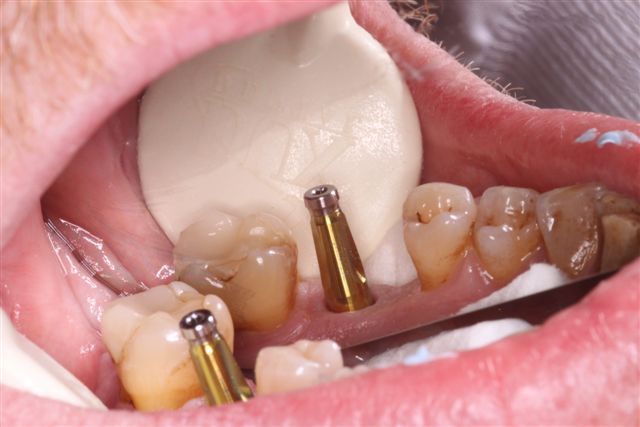

STEP 3 > Finalizing Impression Tray Fit for Impression Coping

STEP 4 > Final Impression with Correct Plus - illustrates excellent detail of impression coping, margin, and surrounding interproximal tissue and structures.